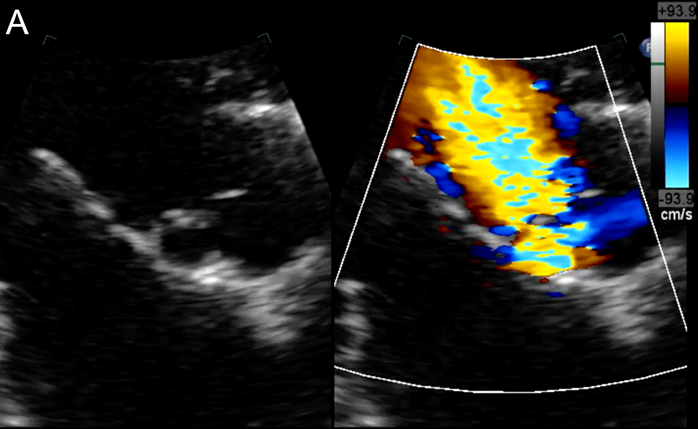

- 2차원 경흉부 심장초음파 검사에서 대동맥 판막 소엽에 부착된 낭종 형태의 구조물이 확인되었습니다. 이 낭종은 직경 8mm의 둥근 무에코 병변으로, 얇은 고에코성 벽을 가지고 있었으며, 좌측 관상동맥 첨판 바로 아래 대동맥 판막 소엽과 밀접하게 접촉해 있었습니다.

- 도플러 검사 결과, 낭종 내부에 액체가 채워져 있으며 대동맥 및 심실 내강과 연결되어 있음이 확인되었습니다. 특히 이완기 동안 낭종 내에서 난류가 관찰되었고, 이는 좌심실 유출로와 연속성을 보여 대동맥 판막 부전의 형성에 기여하는 것으로 나타났습니다.